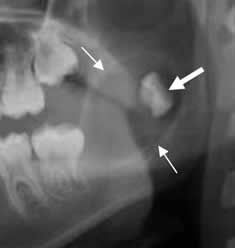

Fig 57. Quiste radicular.

TAC reconstrucción sagital. Lesiones radiolúcidas y redondeadas, que rodean las raíces y corresponden a quistes radiculares. (Flechas delgadas). Adicionalmente existe aumento del espacio periapical, por enfermedad periodontal. (Flecha gruesa).